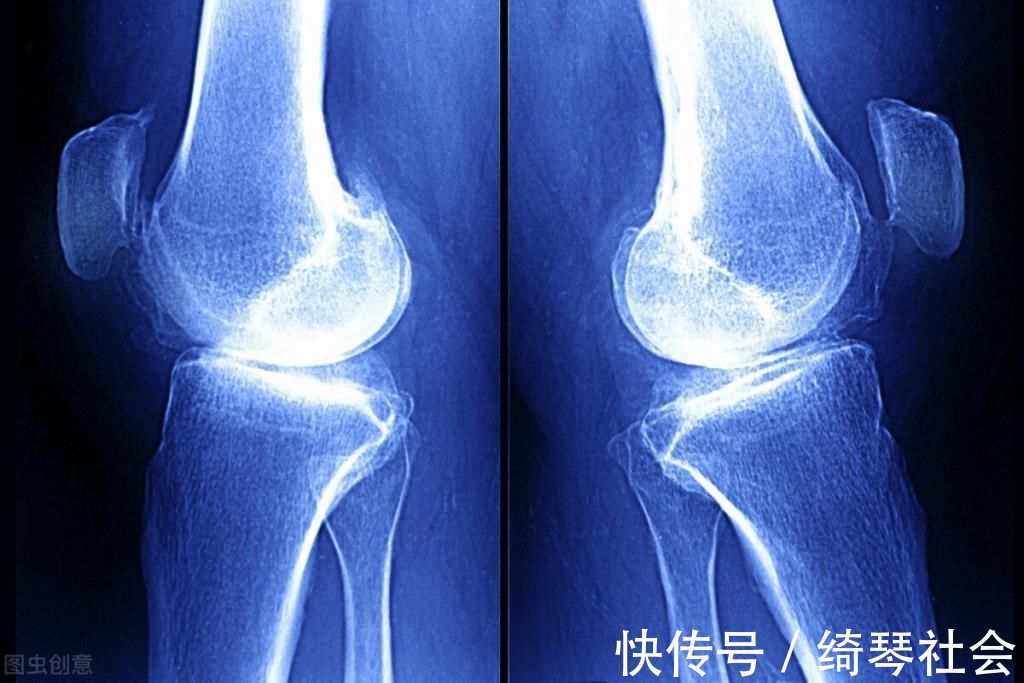

孩子发育较快,破骨细胞的分裂也处于高峰期,容易造成骨骼与肌肉的增长不同步,孩子就会出现腿抽筋或者膝盖疼痛的情况,这也属于种典型的“生长痛”,但在白天的时候疼痛会逐渐消失,除此之外,有可能是因为缺钙造成的手册就要家长及时补充钙质。